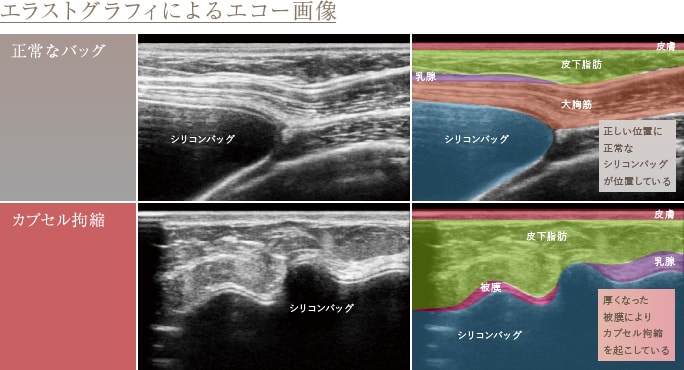

THE CLINIC では、豊胸インプラント挿入後に不安を抱くゲストに対し、乳腺用エコー「エラストグラフィ」による検査をお勧めしています。これによって乳腺の状態はもちろん、インプラントの位置や破損状況、被膜や石灰化の状態等を詳しく確認し、適切な対処法をご提案しています。過去に入れたシリコンバッグプロテーゼなどの豊胸インプラントの状態が気になる方は、是非、最寄りの院までお問い合わせください。

特に多いのが、「カプセル拘縮」に関する相談です。豊胸インプラントをバストに挿入すると、人体は異物であるインプラントを被膜で閉じ込めようとします(ここまでは正常な生体反応です)。問題は、この被膜が必要以上に厚くなったときです。バストの感触が硬くなるだけでなく、形状が異常と思えるようなまん丸(テニスボール状)になり、場合によっては痛みを伴います。「カプセル拘縮」とは、このような障害を指し、豊胸インプラントを挿入した10人に1人の割合で存在すると言われています。